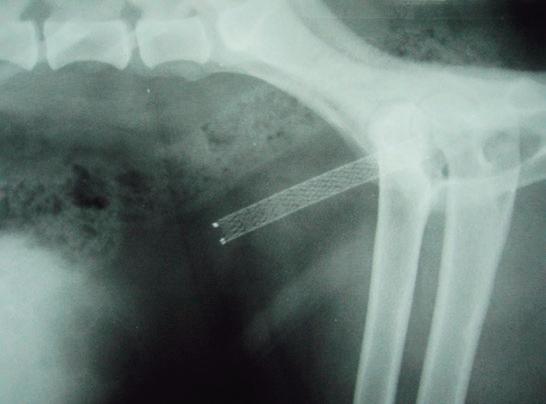

La radiología intervencionista es una especialidad que se encarga del diagnóstico y tratamiento de una gran cantidad de patologías de una forma mínimamente invasiva. Para realizar estos procedimientos es imprescindible disponer del equipamiento adecuado, tener nociones tanto de la instrumentalización como de las diferentes técnicas, y conocer con precisión la anatomía del paciente. Se trata de técnicas cada vez más implementadas en la clínica diaria ya que permiten solucionar diferentes patologías con una menor agresión a nivel tisular, una rápida recuperación, son procedimientos sin dolor, rápidos y seguros, suponen un menor coste respecto a otras cirugías invasivas, y constituyen una alternativa terapéutica a pacientes que no se pueden operar de forma convencional. Entre las más frecuentes destaca el cierre del conducto arterioso persistente, valvuloplastias en estenosis pulmonar, oclusión de shunts portosistémicos, implantación de marcapasos y colocación de stents

En 1953, el Dr. Sven Seldinger describió la colocación percutánea de catéteres vasculares mediante acceso con aguja, técnica que posteriormente se denominó método Seldinger, y que sentó las bases del desarrollo de la radiología intervencionista. En 2005, el Dr. Chick Weisse creó el primer servicio veterinario de radiología intervencionista en la Facultad de Veterinaria de la Universidad de Pensilvania. Desde entonces, esta especialidad ha logrado grandes avances permitiendo el desarrollo de nuevas técnicas y dispositivos, así como un número cada vez mayor de indicaciones para estas técnicas quirúrgicas.

Para realizar la mayoría de los procedimientos quirúrgicos, es imprescindible disponer de un equipo de fluoroscopia, que permite la adquisición rápida de

La radiología intervencionista se realiza mediante un abordaje guiado por distintas técnicas de imagen como, por ejemplo, la ecografía, la fluoroscopia o la tomografía computarizada, para alcanzar la zona a diagnosticar o tratar.

La radiología intervencionista, también conocida como radiología vascular e intervencionista, es una especialidad que se encarga del diagnóstico y tratamiento de una gran cantidad de enfermedades de una manera mínimamente invasiva. Se realiza mediante un abordaje guiado por distintas técnicas de imagen como, por ejemplo, la ecografía, la fluoroscopia o la tomografía computarizada, para alcanzar la zona a diagnosticar o tratar.

La radiología vascular e intervencionista ofrece una alternativa segura y eficaz a la cirugía en muchas enfermedades. Entre sus ventajas para el paciente destaca una menor agresión a nivel tisular, una rápida recuperación, procedimientos sin dolor, rápidos y seguros, un menor coste respecto a otras muchas cirugías con mis-

imágenes basadas en rayos X y posteriormente las convierte en una señal de vídeo en tiempo real. Estas imágenes pueden manipularse ofreciendo funciones como la angiografía de sustracción digital, mapeo vascular y ampliación. Respecto a una radiografía, la exposición de rayos X necesaria para realizar una fluoroscopia es baja, pero debido a la duración de las series de imágenes que habitualmente se toman, el nivel de exposición en los pacientes suele ser elevado. Por lo tanto, es importante controlar el tiempo de exposición y llevar un registro de este. El fluoroscopio debe estar situado en una sala adecuada para su uso seguro, y todo el personal que entre en la sala de fluoroscopia debe protegerse de la radiación utilizando un delantal plomado, protectores de tiroides y gafas plomadas.